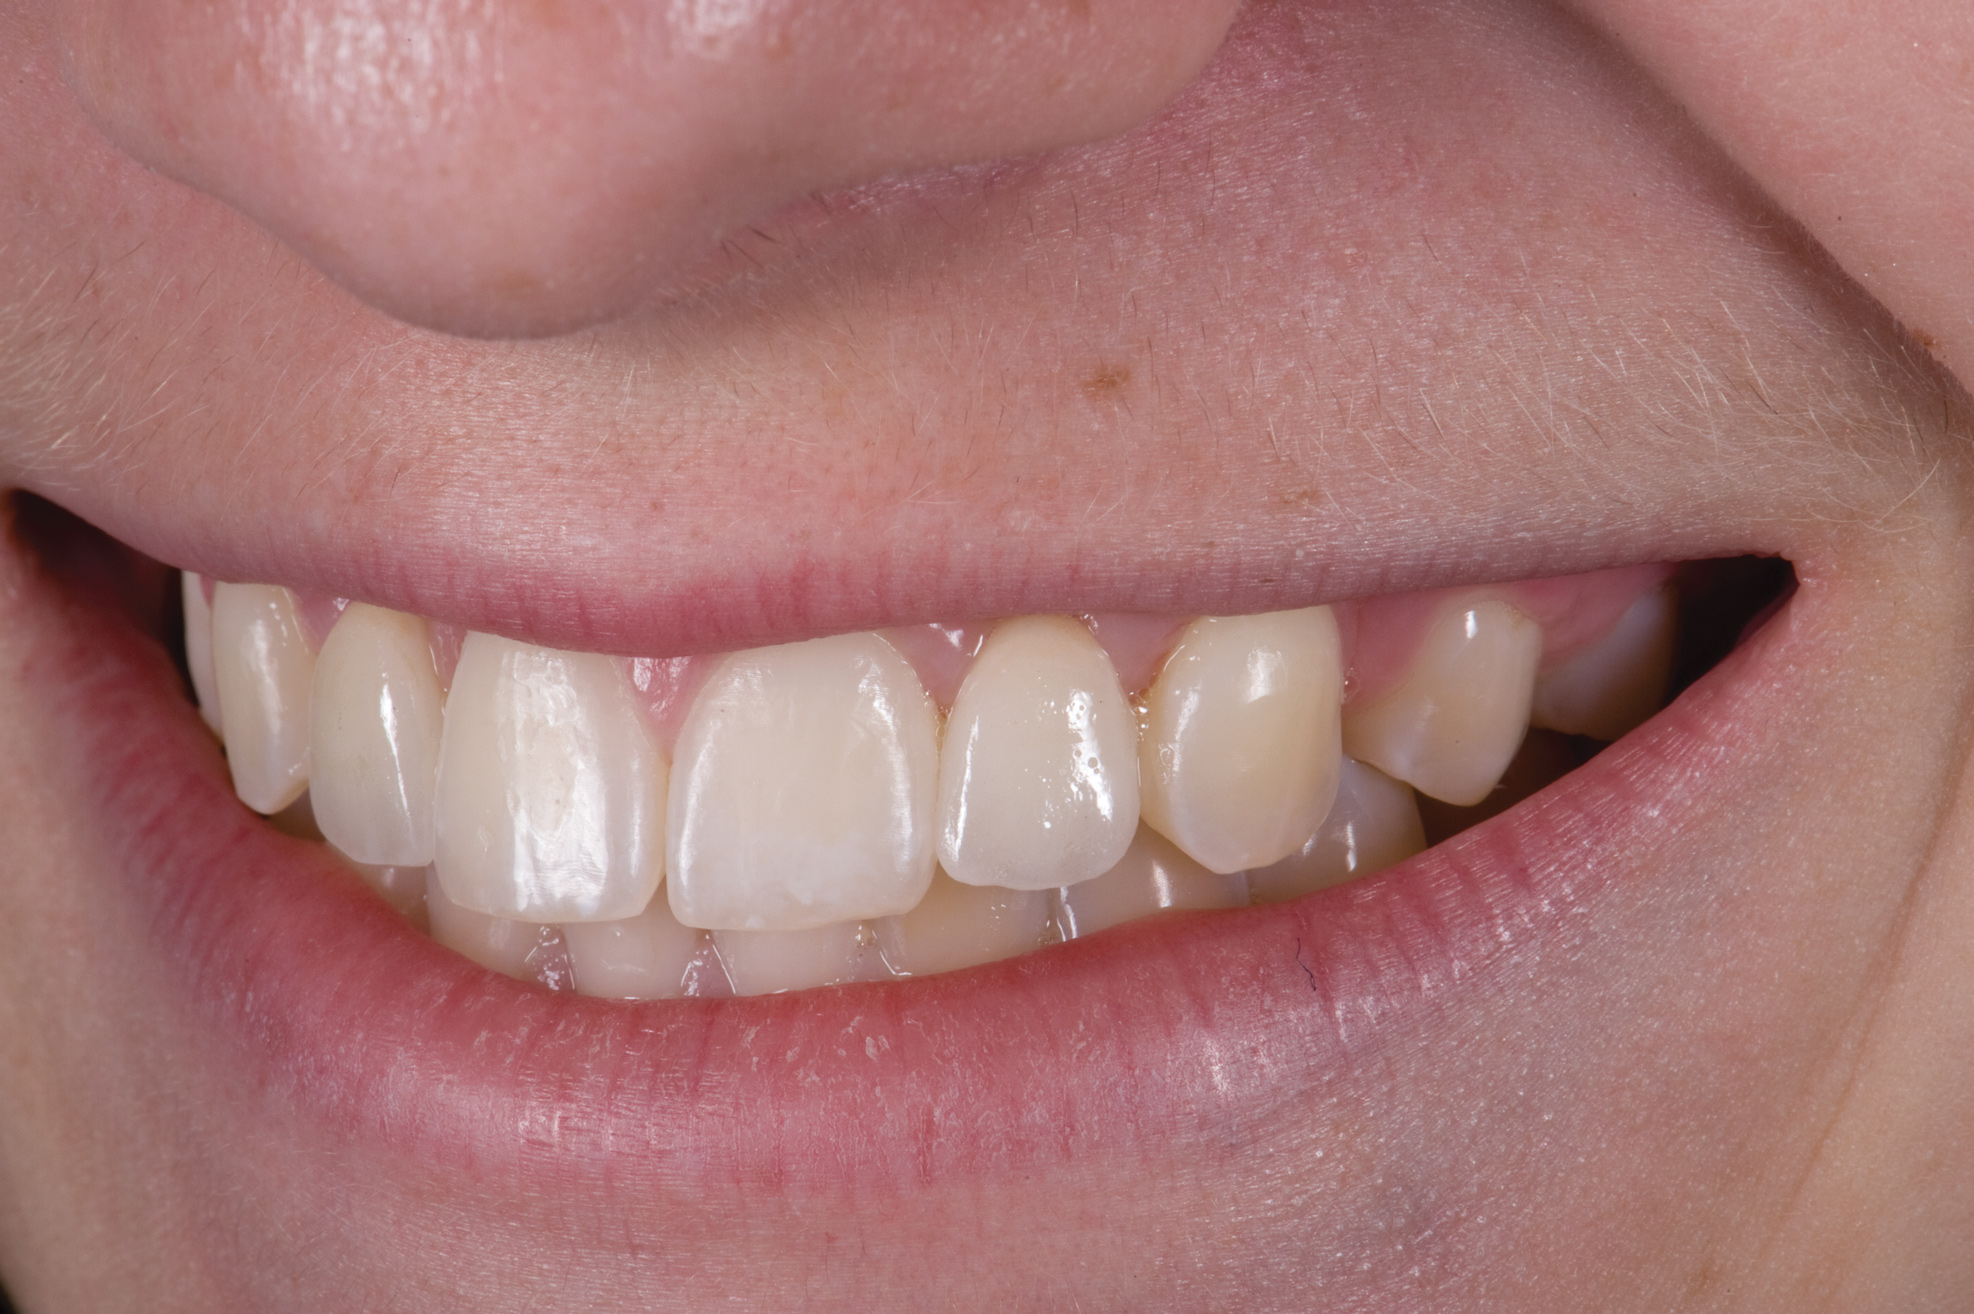

When the patient returned, the fit was evaluated in the mouth. Once verified, the internal surface of the framework was etched with a 9.5% hydrofluoric acid for 90 seconds and then salinized. After etching the enamel surface with phosphoric acid for 30 seconds and applying the primer (Single Bond Plus, 3M ESPE) to both the internal surface of the framework and the enamel, the zirconia bridge was bonded with a dual-cure resin cement (RelyX ARC, 3M ESPE). After the procedure, the patient ended up with a long-term, high-strength esthetic restoration advantaged by the bonding potential of feldspathic ceramic (Figure 20 through Figure 24). Six years after placement, the prosthesis had remained in place with no complications.

Fig 20. Facial view of final single-wing, modified zirconia resin-bonded bridges.

Figure 20

Fig 21. Smile view.

Figure 21

Fig 22. Right lateral view.

Figure 22